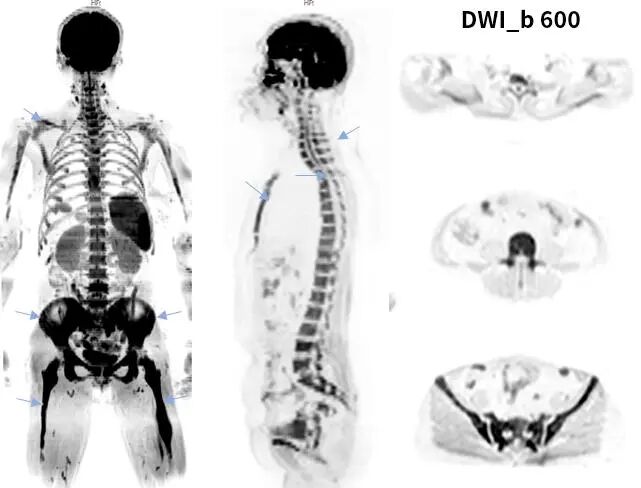

PET_like

类PET又称“背景抑制的全身扩散加权成像(DWIBS)”,该技术能够一次性全身大范围扫描,可以获得全身肿瘤筛查、良恶性肿瘤的鉴别、肿瘤TNM分期及疗效随诊等诊断信息,其成像效果和临床意义与PET有相同的效果。